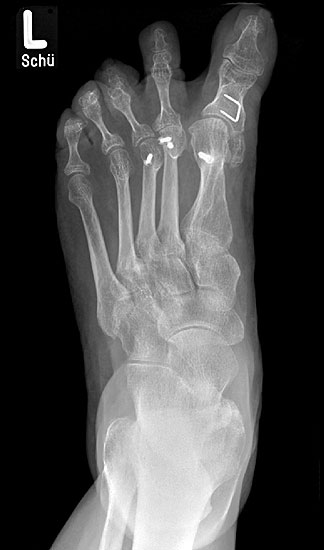

11"> Der Hallux varus Winkel  <a class=11" title="Der Hallux varus Winkel 11" srcset="/assets/images/2/4-vk3bypbg5s5x7zc.jpg 1x, /assets/images/3/4-aax2sd1hrpnrvrb.jpg 1.452x" width="270" height="240" loading="lazy">

Abbildung 3

Die bildgebende Diagnostik hilft bei der Klärung der Ätiologie und des Ausmaßes der Fehlstellung. Hierzu sind Röntgen­aufnahmen im Stand in mindestens zwei Ebenen unter Belastung des Fußes erforderlich. Mit Hilfe der belasteten Röntgenaufnahmen wird der Hallux-varus-Winkel, d. h. den Winkel zwischen der Achse der Grundphalanx der Großzehe und der Achse des ersten Mittelfußknochens bestimmt, sowie etwaige Rotationsfehlstellungen des 1. Strahls verifiziert. Eventuelle knöcherne Fehlanlagen bei kongenitalen Deformitäten können hierdurch ebenfalls verifiziert werden.

Weitere Beurteilungskriterien sind:

• degenerative Veränderungen des MTP I

• Kongruenz des MTP I- Gelenkes

• Form und Stellung des Mittelfußköpfchens I

• Ausprägung der Pseudoexostose.

• PASA-Winkel, d. h. der periphere Artikulationswinkel des Großzehengrundgelenkes.

Zur Klärung der Ätiologie wird der intermetatarsale Winkel zwischen Os metatarsale I und II bestimmt. Ist dieser kleiner als 5° oder gar negativ, ist eine Varusstellung der Großzehe oft die Folge.

Am Röntgenbild des belasteten Fußes bestimmt man die Lage der Sesambeine zum 1. Mittelfußköpfchen.

Anhand der Röntgenaufnahme lassen sich die Folgen einer eventuellen Voroperation bestimmen, wie z. B. die Stellung des ersten Mittelfußköpfchens, des ersten Metatarsale nach Korrekturen der Achse bei einer Hallux-valgus-Operation. Mitunter bestehen Nekrosen des Mittelfußköpfchens oder eine übermässige Resektionen der Pseudoexostose. Auch die Länge des 1. Metatarsale kann von Interesse sein, z. B. nach einer Lapidusarthrodese (Johnson 1994).